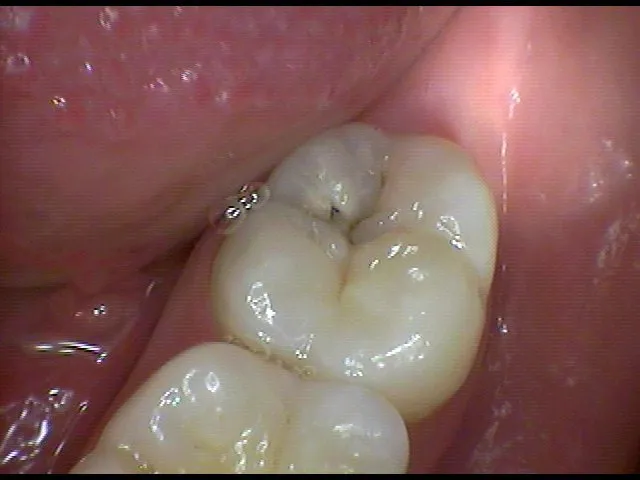

When you visit our Hanoi clinic, I start every whitening case with a consultation. I examine your teeth to identify existing restorations, check for cavities or gum disease, and discuss your whitening goals. This matters because whitening only works if your oral health is solid.

I use a shade guide to document your current tooth color. This baseline lets us measure your progress accurately. I’ve found that patients love seeing the before and after comparison, especially when they’ve achieved the 6 to 8 shade improvement we typically see.